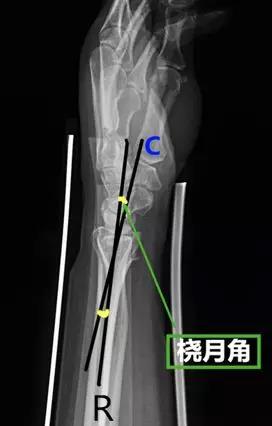

腕关节

- 掌倾角:即在腕关节侧位片上桡骨最远端尺侧和桡侧顶点的连线与桡骨纵轴线的垂线的夹角。

- 正常值:10°~15°(11°±2°)

- 临床意义:改变主要提示桡骨远端骨折,在正位片上桡骨短缩>5mm或在侧位片上背侧成角>20°提示预后较差。

- 桡骨尺偏角:在桡骨、尺骨的下尺桡关节面作一水平线,此线与桡骨远端关节面的切线所形成的夹角。

- 正常值:20°~25°

- 临床意义:若桡骨尺偏角改变,提示腕关节脱位或者桡骨远端骨折。

- 尺腕角:在腕关节正位片作月骨和三角骨的外缘切线,并作尺骨远端关节面的切线,此两线所形成的夹角。

- 正常值:21°~51°

- 临床意义:若尺腕角改变,提示腕骨骨折或腕关节脱位。

- 腕骨角:在腕关节正位片上分别作手舟骨、月骨的切线和月骨、三角骨的切线,此两线的夹角。

- 正常值:130°

- 临床意义:腕关节骨折、脱位时腕骨角增大;腕骨角减小见于Madelung 畸形和卵巢发育不全。

- 桡头角:腕部侧位片上桡骨和头状骨中轴线的夹角。

- 正常值:6°~26°

- 临床意义:>26°提示腕关节不稳。

- 桡月角:在腕部侧位片上桡骨和月骨(近端与远端)中轴线的夹角。

- 正常值:0°~15°

- 临床意义:屈曲>15°提示掌曲不稳,背伸>10°提示背伸不稳。

- 头月角:腕部侧位片上头状骨和月骨中轴线的夹角。

- 临床意义:>20°提示腕关节不稳。

- 舟月角:在腕关节侧位片舟骨与月骨(近端与远端)中轴线的夹角。

- 正常值:30°~60°

- 临床意义:舟月角>70°提示腕背伸不稳,<30°提示腕掌屈曲不稳;>60°或移位>1mm,需要对舟骨进行切开复位内固定;舟月间距<3mm,间距>3mm提示舟月韧带撕裂。

- 桡舟角:在腕关节侧位片桡骨与舟骨(掌侧与背侧)中轴线的夹角。

- 正常值:55°~75°

- 临床意义:>75°提示腕关节不稳。